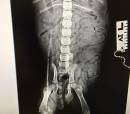

Olli (BLK / WHITE CHIHUAHUA PUPPY)

Latest Updates

Help us, help him!

Your donation will help Olli (BLK / WHITE CHIHUAHUA PUPPY) recover.